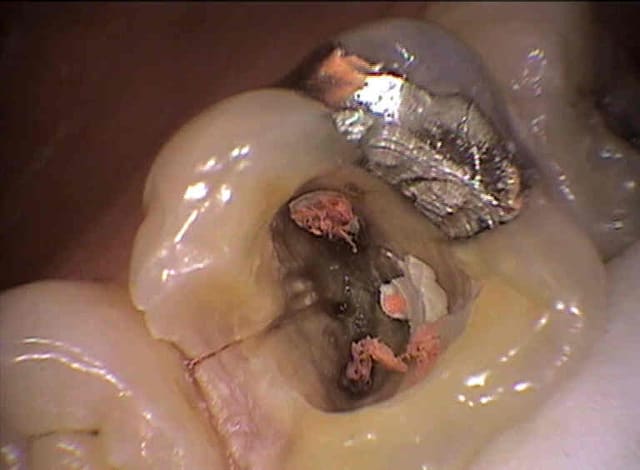

Je relance ce post pour avoir votre avis sur ce cas : jeune femme 25 ans en urgence douleur sourde d'apparition brutale sur 16 dévitalisée .Test morsure positif et papille mesiale enflammée , je démonte l'obturatio et voila ce que je mets en évidence ( il y a en plus un mv2 non obturé).Extraire d'emblée cette dent me fait mal au coeur : y aurait il un traitement à tenter ou que vous auriez réalisé avec succes ? ( la felure ne traverse pas entièrement la dent: localisée en mésiale )

Merci.